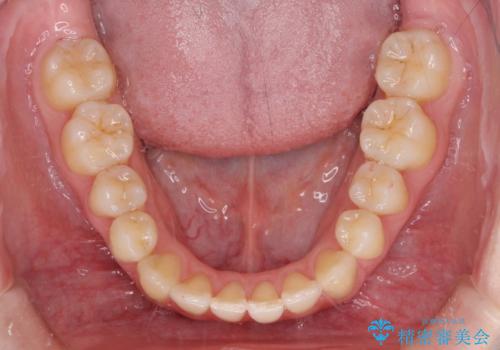

- ちょっとしたデコボコを整えたいとのことで来院された患者様です。

歯列不正は軽微であったため、インビザライン・ライトにより、費用を抑えて矯正治療を行うこととしました。

上下前歯の捻れが改善され、患者様には大変満足していただきました。